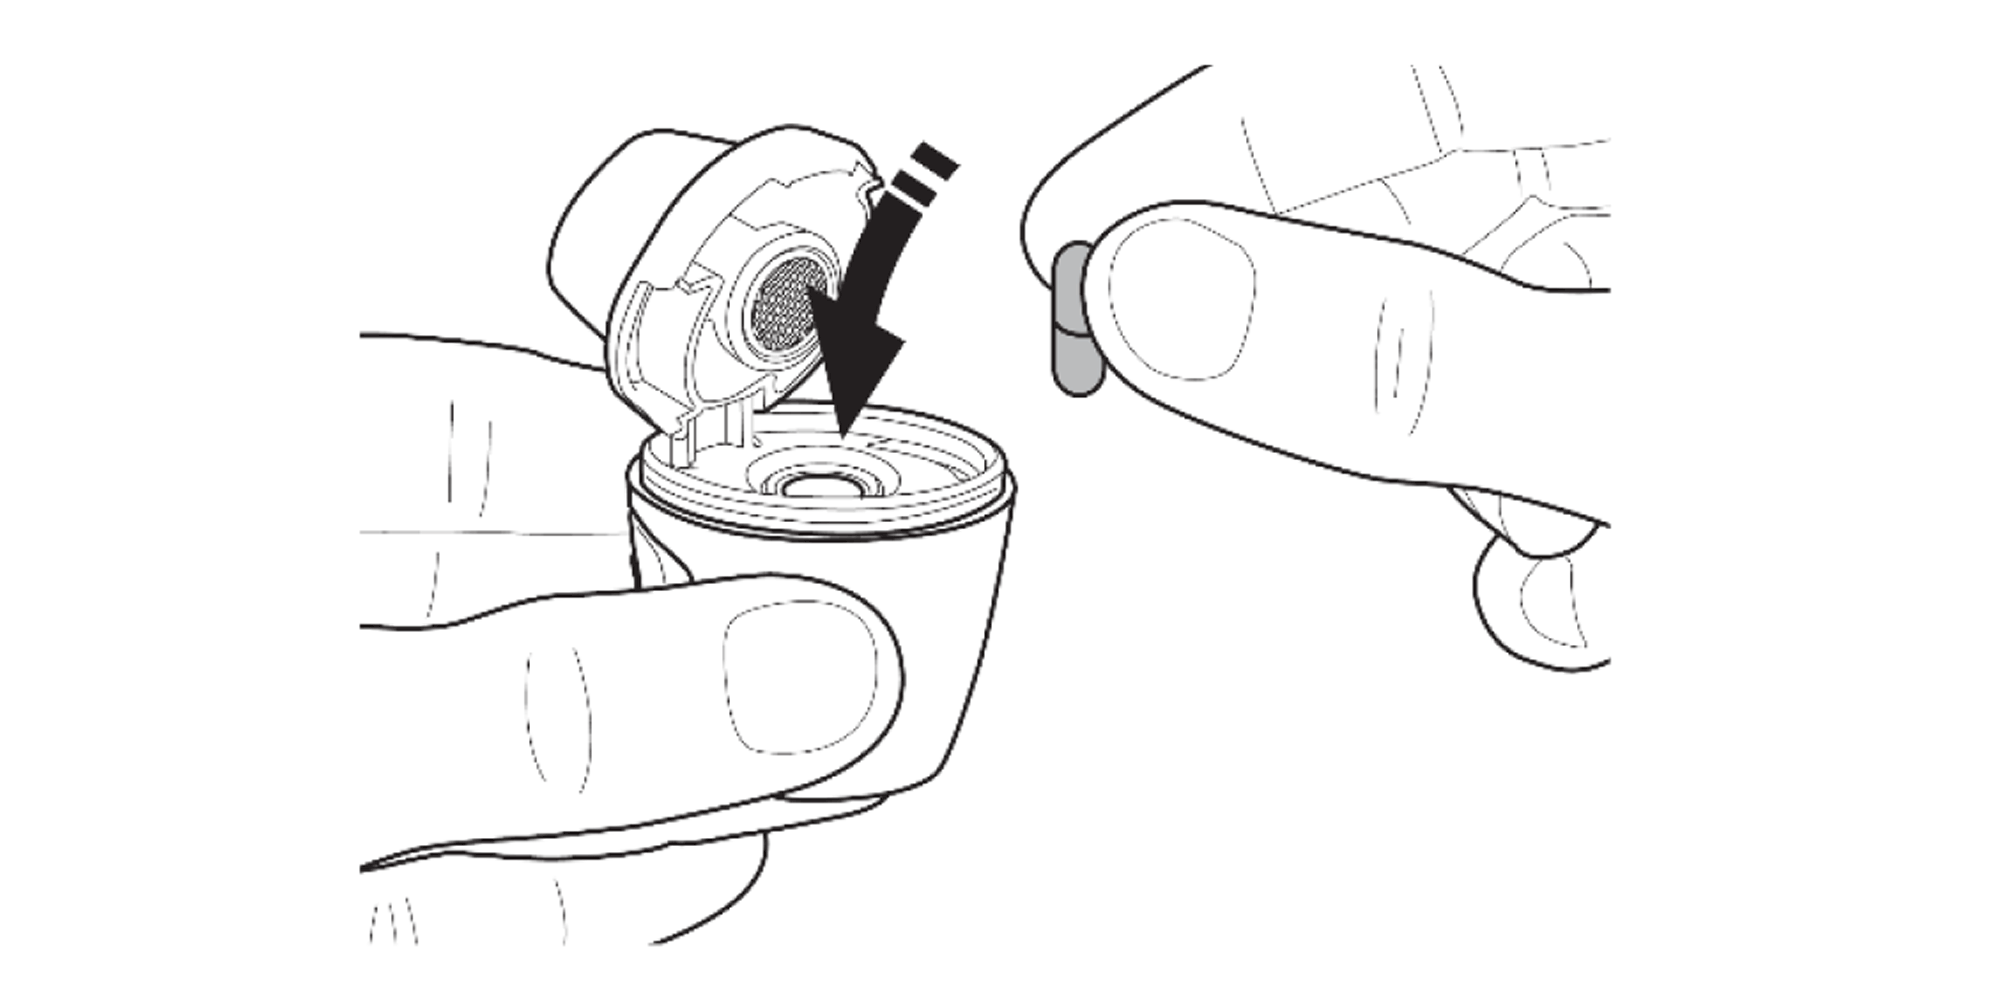

Remove the capsule from the blister and insert it into the capsule chamber.